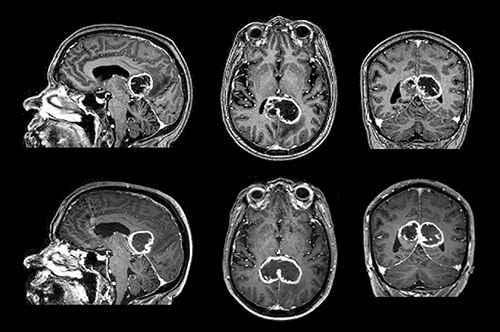

Figuren viser kontrastforsterkede T₁-vektede MR-bilder av et sommerfugl-gliom med kraftig perifer kontrastoppladning og sentral nekrose, typisk for et glioblastom. Sommerfugl-gliomer infiltrerer oftere fremre del av corpus callosum (≈ 60  %), mens midtre del (≈ 30  %) og bakre del (≈ 10  %) er sjeldnere (1). Symptomatisk kan slike svulster ofte resultere i såkalte frakoblingssyndromer som aleksi, agrafi og apraksi, i stedet for ordinære sensomotoriske utfall. Ensidig apraksi kan for eksempel ses dersom språkområdene på venstre side ikke lenger er forbundet med de motoriske områdene i høyre hjernehalvdel. Pasienten klarer da ikke å utføre kommandoer med venstre hånd, men klarer det godt med høyre hånd.

Nederste del av figuren viser den samme svulsten etter 16 dager, der den har vokst fra 27,4 cm³ til 37,6 cm³, en vekst på 37  %. Dette tilsvarer en doblingstid på 32 dager, forutsatt eksponentiell vekst. I litteraturen er det få systematiske undersøkelser av veksthastighet og doblingstid av glioblastomer in vivo. De få studiene som finnes angir doblingstider på 10 – 95 dager.